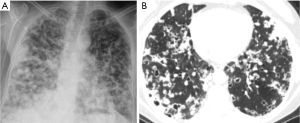

Miscellaneous